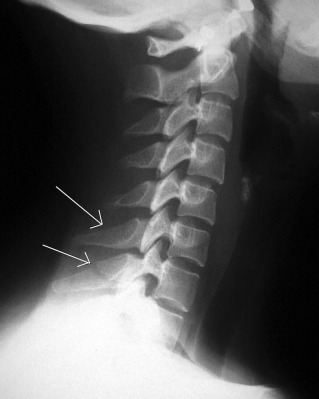

Lateral C-Spine: Eval Criteria

Cervical vertebral bodies, intervertebral joint spaces, articular pillars, spinous processes, and zygapophyseal joints demoed

C1 through C7-T1 intervertebral joint spaces are clearly seen

R and L articular pillars and zygapophyseal joints should be superimposed for each vertebra

Bodies free of superimposition of the articular pillars

Spinous process seen in profile

Lateral C-Spine: Is this Image Good?

No

C7 is obscured

C1 anatomy is clipped and spine is not centered

Need to center higher and more anterior

Tilt leads to poor superimposition of zygapophyseal joints

Used AEC but it wasn’t centered to bone (underexposed)